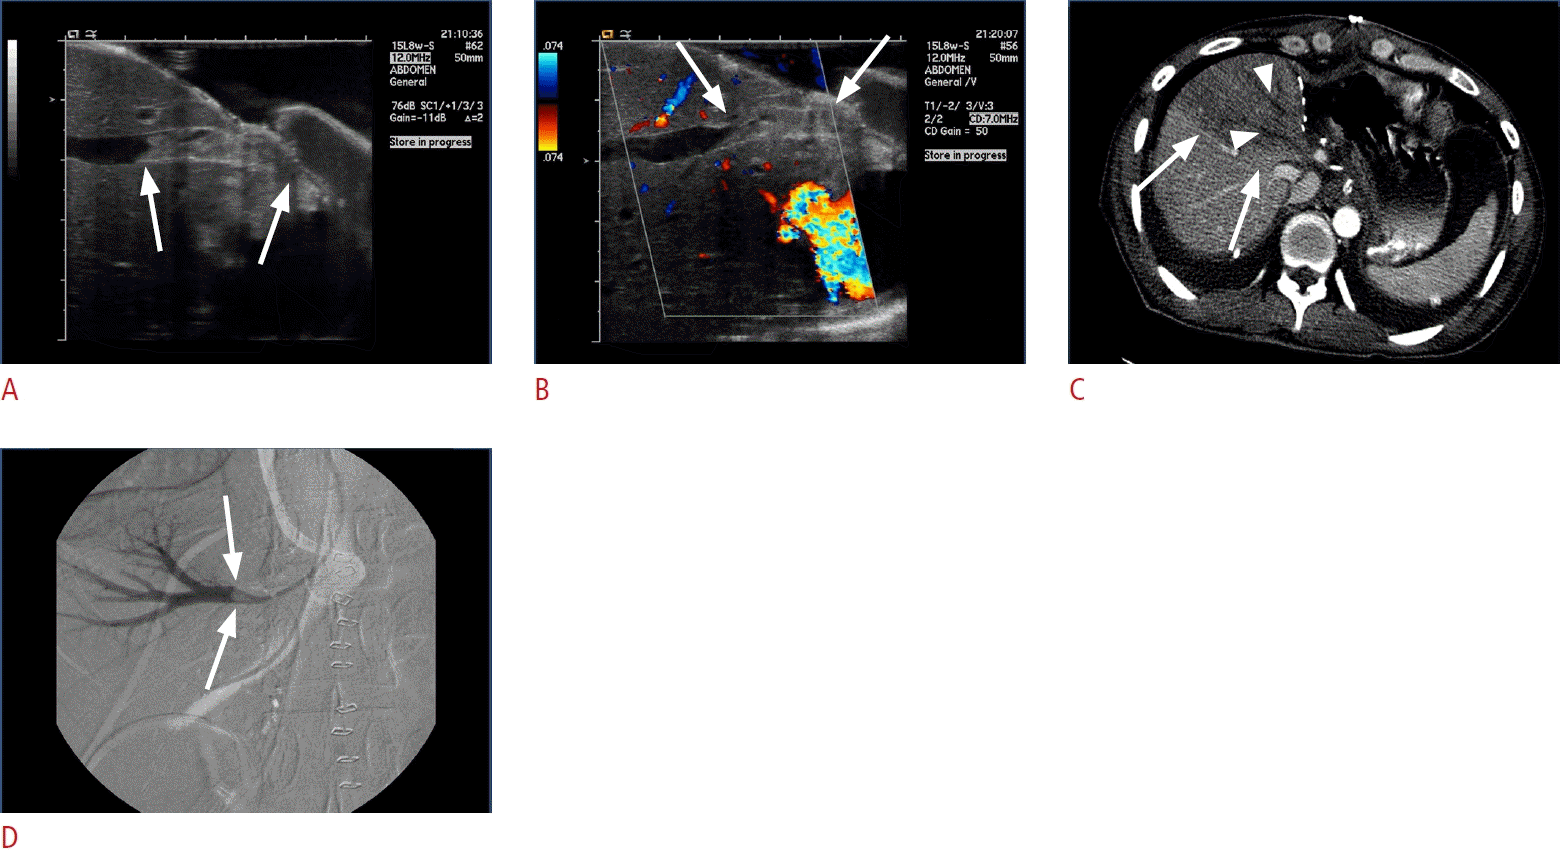

Fig. 8.

Tight stenosis at the venous anastomosis.

A. Grayscale intraoperative ultrasonogram shows tight stenosis at the anastomosis between right hepatic vein and inferior vena cava (arrows). Color Doppler ultrasonogram (B) and Doppler spectrogram (C) show focal aliasing of color signal at anastomosis and monotonous venous spectral waveform in the graft, which represent significantly disturbed hepatic venous-outflow. D. Computed tomography maximum intensity projection image obtained during hepatic venous phase on postoperative day 1 demonstrate tight stenosis at the anastomosis (arrow) between the right hepatic vein and inferior vena cava.

Fig. 9.

Thrombus in interposed venous conduit.

A, B. Grayscale (A) and color Doppler (B) intraoperative ultrasonograms of the middle hepatic vein tributary in segment 8 (V8) and interposing venous conduit, show echogenic intraluminal thrombus (arrows) and color signal void. C. Axial computed tomography scan obtained during hepatic arterial phase on postoperative day 1 demonstrates nonopacification of V8 (arrowheads) and well-demarcated, wedge-shaped area of hypoattenuation (arrows) in right anterior sector that corresponds to draining territory of V8. Vertex of wedge-shaped low attenuation area typically points to inferior vena cava. D. Hepatic venography reveals intraluminal thrombus of the middle hepatic vein tributary in V8, seen as filling defect (arrows). Endovascular stent placement was performed.